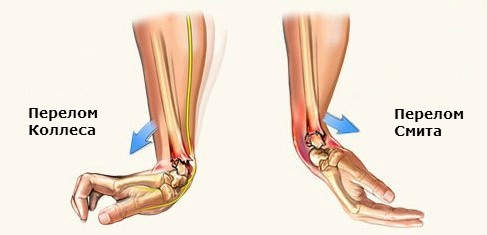

- Смита, или сгибательный. Случается, когда человек падает на кисть, согнутую в сторону тыльной поверхности предплечья. В результате костный отломок лучевой кости смещается к наружной поверхности предплечья;

- Колеса, или разгибательный. Происходит в том случае, когда пострадавший падает на ладонную поверхность кисти. В результате имеет место переразгибание в лучезапястном суставе, и костный отломок смещается в сторону тыльной поверхности предплечья.

Как видно из описания, перелом Смита и Колеса являются зеркальным отображением друг друга.